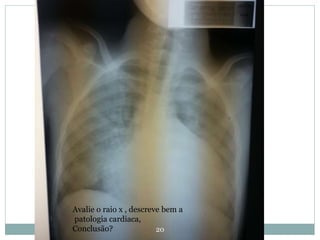

Avalie o raio x , descreve bem a

patologia cardiaca,

Conclusão?

20 Avalie o raiox , descreve bem a patologia cardiaca, Conclusão?